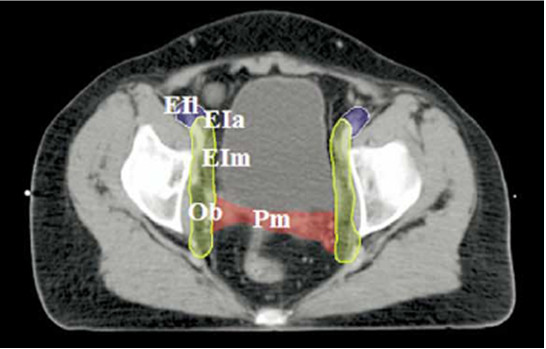

W klinicznym obszarze napromieniania (CTV) raka szyjki macicy na przedstawionym rysunku znajdują się następujące struktury: